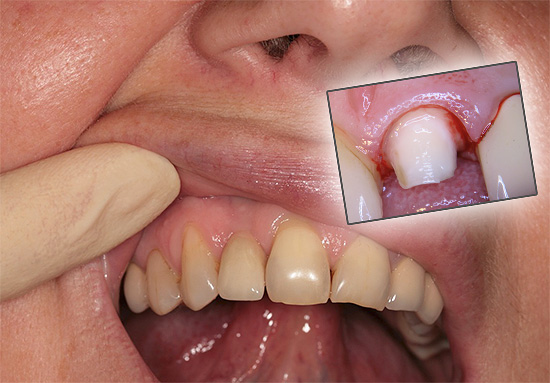

Há situações em que uma gengiva começa a doer sob uma coroa, não um dente. Uma coroa fixada em um dente pode passar excessivamente sob a gengiva com sua borda ou, inversamente, pode não atingir significativamente sua borda.

Na primeira opção, um trauma permanente com uma aresta aguda forma uma inflamação local, e a inflamação é acompanhada de dor, que "dá" ao dente. Como resultado, parece à pessoa que é o dente que dói sob a coroa, embora a causa esteja nas gengivas.

A foto abaixo mostra um exemplo de inflamação das gengivas em contato com as coroas:

Na segunda opção (quando a coroa não atinge as gengivas), geralmente a dor não ocorre logo. Atrasos freqüentes de comida entre a gengiva e a borda da coroa podem causar a mesma inflamação e dor no futuro como no primeiro caso, mas a cárie dentária provavelmente se desenvolverá, levando à destruição gradual dos tecidos duros sob a coroa com o aparecimento de uma reação dolorosa a calor, frio, pressão e pressão. outros irritantes.